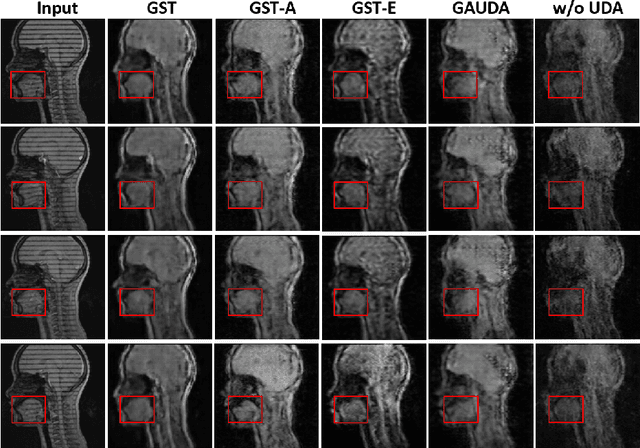

Abstract:Self-training is an important class of unsupervised domain adaptation (UDA) approaches that are used to mitigate the problem of domain shift, when applying knowledge learned from a labeled source domain to unlabeled and heterogeneous target domains. While self-training-based UDA has shown considerable promise on discriminative tasks, including classification and segmentation, through reliable pseudo-label filtering based on the maximum softmax probability, there is a paucity of prior work on self-training-based UDA for generative tasks, including image modality translation. To fill this gap, in this work, we seek to develop a generative self-training (GST) framework for domain adaptive image translation with continuous value prediction and regression objectives. Specifically, we quantify both aleatoric and epistemic uncertainties within our GST using variational Bayes learning to measure the reliability of synthesized data. We also introduce a self-attention scheme that de-emphasizes the background region to prevent it from dominating the training process. The adaptation is then carried out by an alternating optimization scheme with target domain supervision that focuses attention on the regions with reliable pseudo-labels. We evaluated our framework on two cross-scanner/center, inter-subject translation tasks, including tagged-to-cine magnetic resonance (MR) image translation and T1-weighted MR-to-fractional anisotropy translation. Extensive validations with unpaired target domain data showed that our GST yielded superior synthesis performance in comparison to adversarial training UDA methods.

Abstract:Self-training based unsupervised domain adaptation (UDA) has shown great potential to address the problem of domain shift, when applying a trained deep learning model in a source domain to unlabeled target domains. However, while the self-training UDA has demonstrated its effectiveness on discriminative tasks, such as classification and segmentation, via the reliable pseudo-label selection based on the softmax discrete histogram, the self-training UDA for generative tasks, such as image synthesis, is not fully investigated. In this work, we propose a novel generative self-training (GST) UDA framework with continuous value prediction and regression objective for cross-domain image synthesis. Specifically, we propose to filter the pseudo-label with an uncertainty mask, and quantify the predictive confidence of generated images with practical variational Bayes learning. The fast test-time adaptation is achieved by a round-based alternative optimization scheme. We validated our framework on the tagged-to-cine magnetic resonance imaging (MRI) synthesis problem, where datasets in the source and target domains were acquired from different scanners or centers. Extensive validations were carried out to verify our framework against popular adversarial training UDA methods. Results show that our GST, with tagged MRI of test subjects in new target domains, improved the synthesis quality by a large margin, compared with the adversarial training UDA methods.